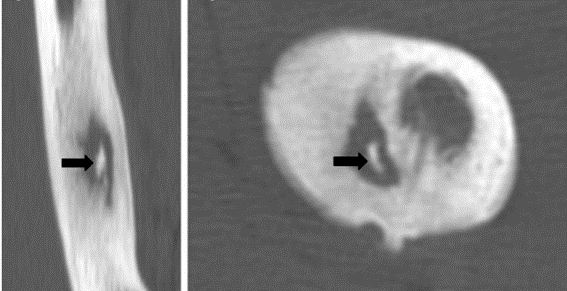

Diversos exame colaboram para diagnóstico de um sequestro ósseo, dentre eles estão as radiografias, tomografia computadorizada e ressonância magnética. As radiografias normalmente mostram apenas os sequestro maiores devido a baixa ser imagens bidimensionais. A tomografia é considerada o melhor exame para ver o fragmento destacado. Já a ressonância magnética é utilizada em conjunto para avaliar as características do sequestro ósseo, como por exemplo presença de irrigação sanguínea no mesmo.

Imagem tomográfica de um sequestro ósseo.

Fonte: https://pubmed.ncbi.nlm.nih.gov/20571796/